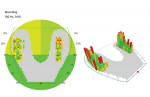

At the conclusion of the orthodontic treatment the patient was extremely satisfied with the results, as the gaps in his smile were fully closed (Figure 7). However, he mentioned that his "bite felt off" but was unsure why. The clinician suspected that this was due to a premature anterior contact caused by retrusion of the patient's upper anterior teeth that had been done in order to close his gaps. Using the OccluSense, the clinician pinpointed the exact areas of occlusal interferences and equilibrated the patient's occlusion to get him into an occlusion that was similar to his pretreatment occlusion (Figure 8 and Figure 9). This was made possible by having the pretreatment OccluSense measurement that had been taken at the beginning of treatment and which served as a reference when adjusting the post-treatment occlusion.